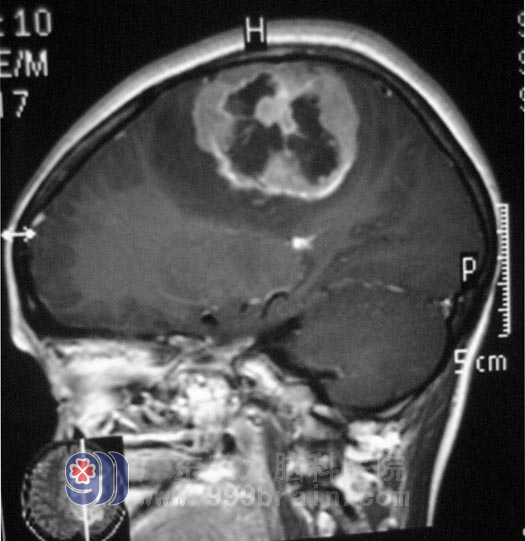

上图的左侧额顶叶占位,让两天前还在小区里教舞友们跳舞的陈姐,现在却走不了路。http://www.999brain.com/

广东三九脑科医院综合神经外科鲁明主任结合陈姐的临床症状及外院CT,考虑左侧额顶叶占位性病变伴有钙化,中线移位,病人精神、食欲差,进一步MR检查明确了病灶范围。 5月14日,陈姐在全麻下行左侧额顶部镰窦旁占位切除术。黄色肿瘤组织,脑组织被挤压向左侧,包膜完整,质中偏软,血运较丰富,广基与大脑镰相连,由鲁明主任主刀,在显微镜下予肿瘤切除: